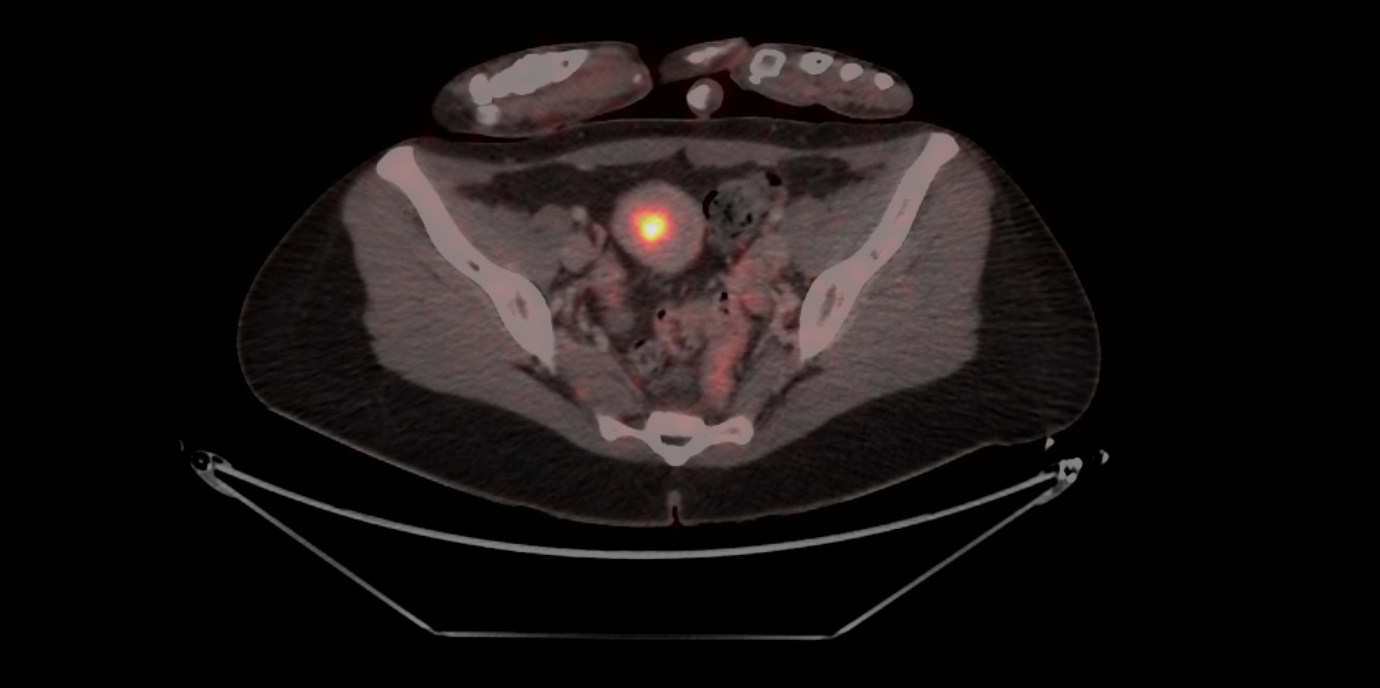

*) Die Klassifizierung des Tumors erfolgt u.a. auch nach histologischen und molekularen Methoden. Das Bestimmen des MMR-Status (mismatch-repair; Mutationen, die die DNA-Reparatur betreffen) mittels Immunhistochemie kann eine entscheidende Relevanz für die Therapieplanung beim lokal fortgeschrittenen und/oder rezidivierten Endometriumkarzinom haben. pMMR = Mismatch-Repair-profizient, dMMR = Mismatch-Repair-defizient.(27.11.2024, Text: D. Heidegger, Bild: Univ.-Klinik für Nuklearmedizin Innsbruck/Rossetti)